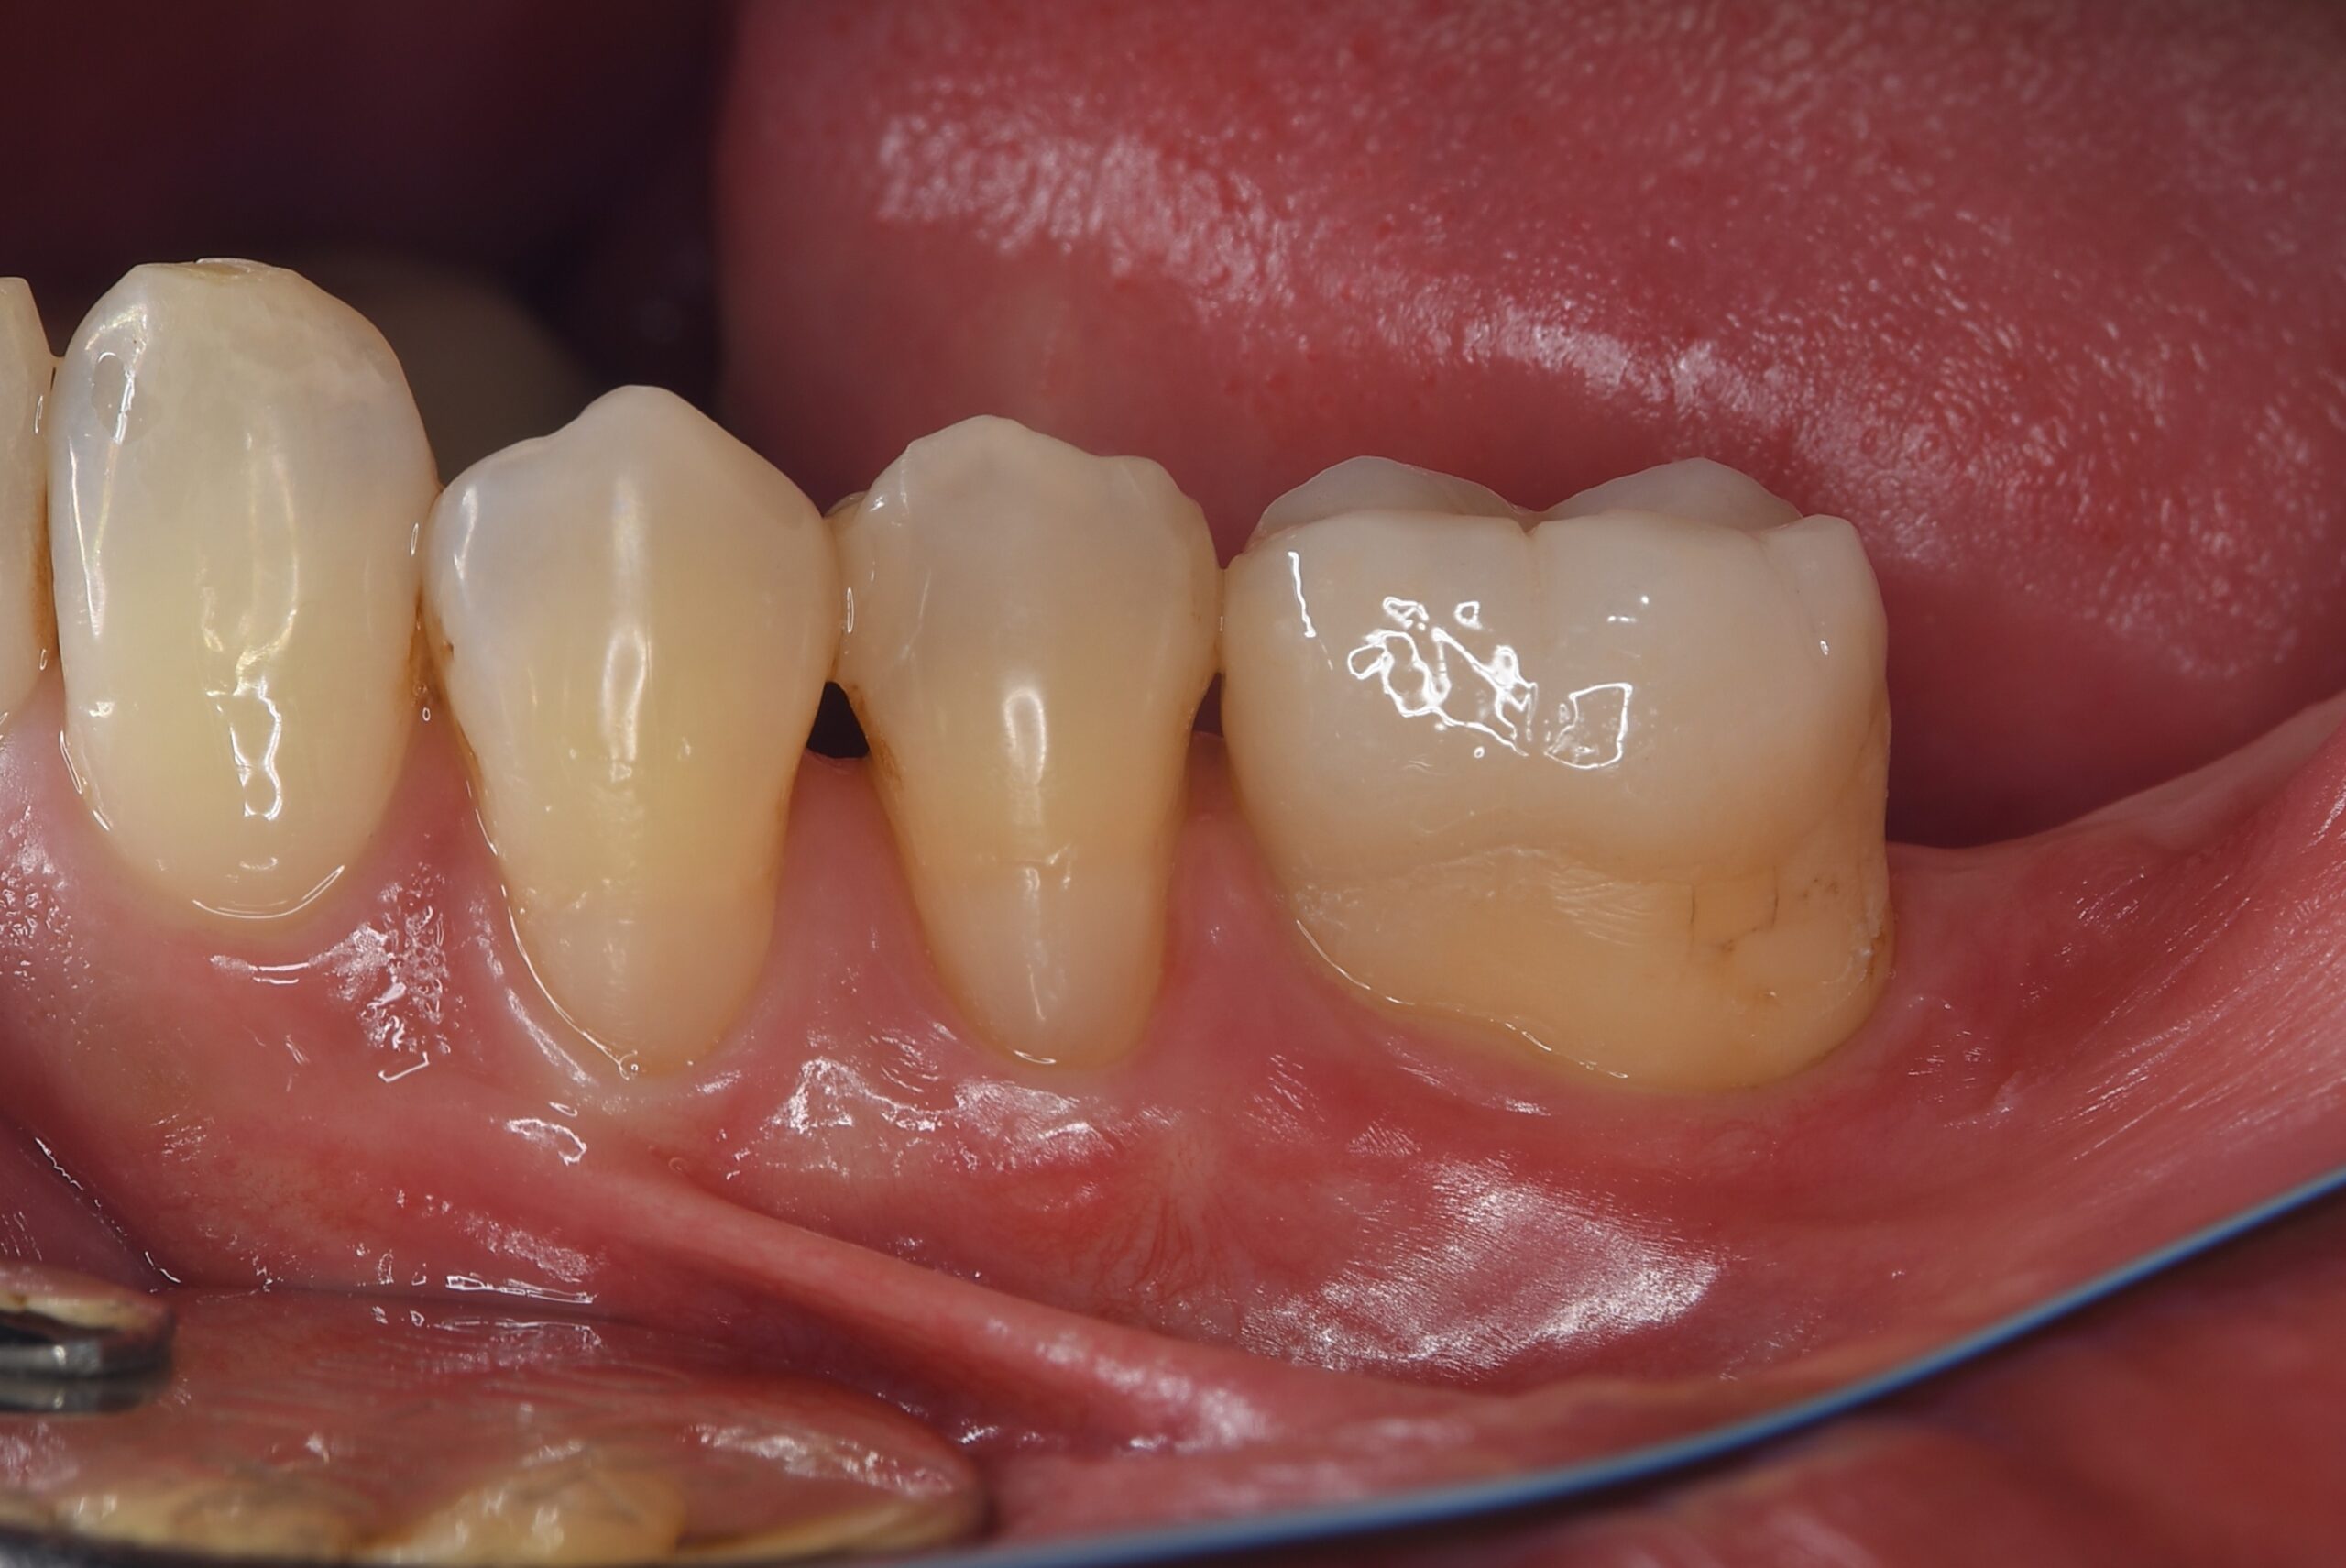

右下親知らずを右下第二大臼歯へ移植

| 患者様データ | 20代 女性 |

| 来院時の主訴 | 「右下奥歯で噛むと痛い。」 |

| 医院の診断 | 歯根破折 |